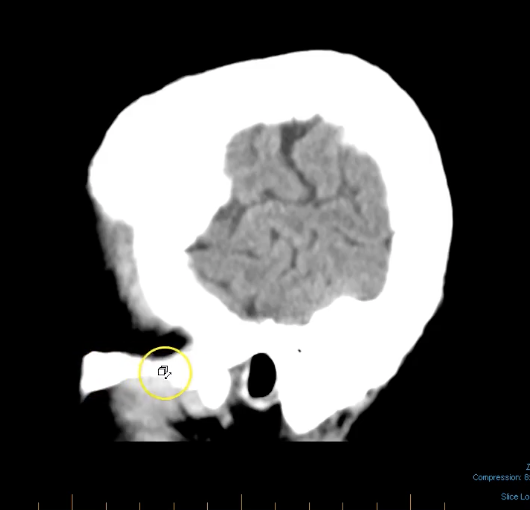

term image

structure down the midline of brain- falx cerebri

when assessing for midline shift of brain will form a tent superior to cerebellum